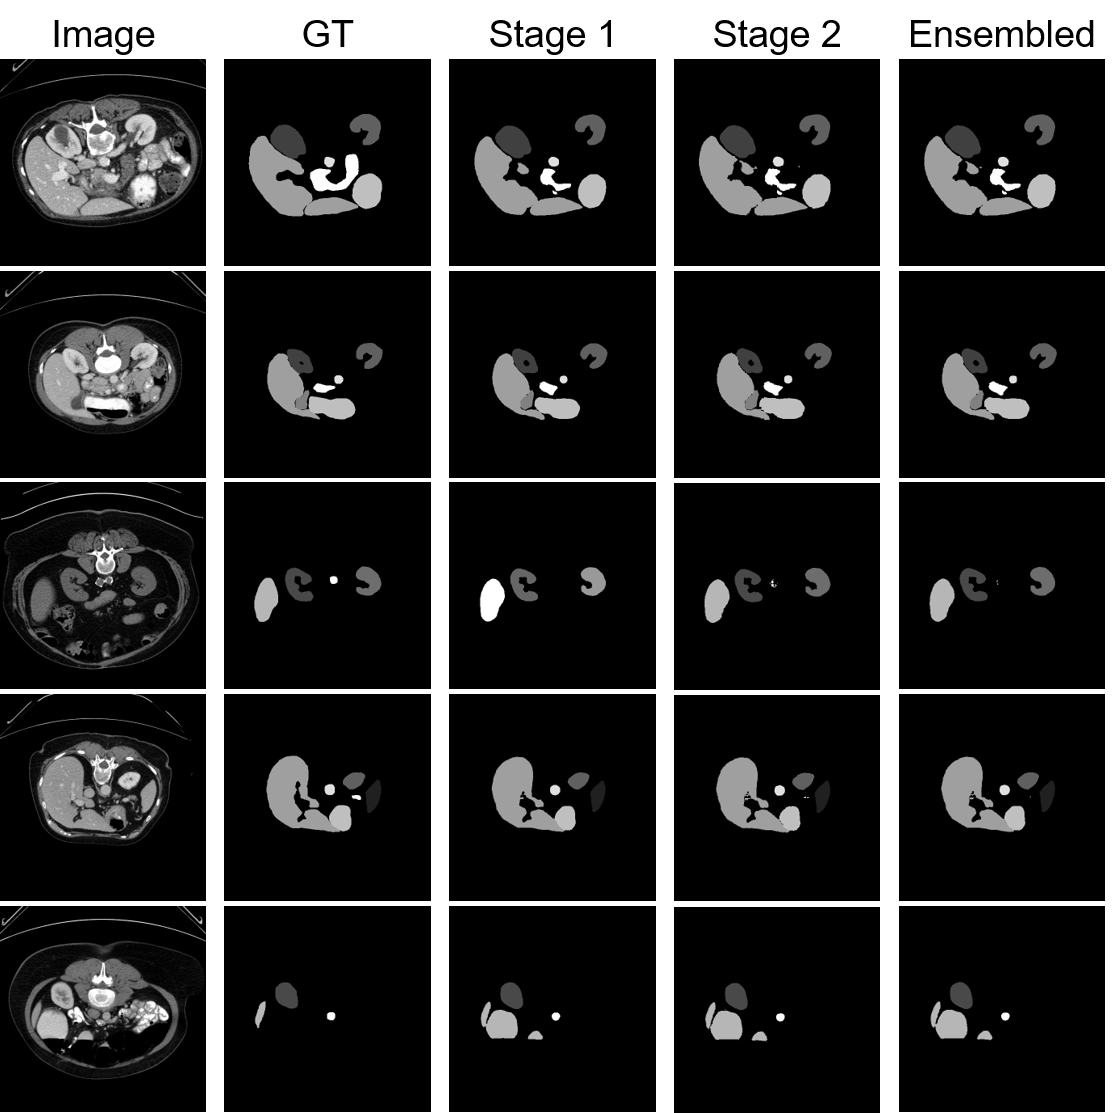

C.3 Visualization on 2 stages

Here we present the visualization of outputs from different stages. As shown in Figure 8, benefit from the joint training design, both of the 2 stages perform excellent segmentation predictions. In row 5, we present a failure case where stage 2 takes an erroneous prediction from stage 1 as the prior and mistakes a background region to kidney. However, in most cases, the stage-2 prediction takes and corrects stage-1 results as the prior to generating finer segmentation, which especially can be reflected from small organs like Pancreas, as shown in rows 3 and 4.

Refer to caption

Figure 8: Visualization of the outputs from different stages. First column: raw image. Second column: ground truth. Third column: stage-1 output. Fourth column: stage-2 output. Fifth column: ensembled output from 2-stage outputs. The last row shows failure cases where stage 2 takes an erroneous prediction from stage 1 as the prior.